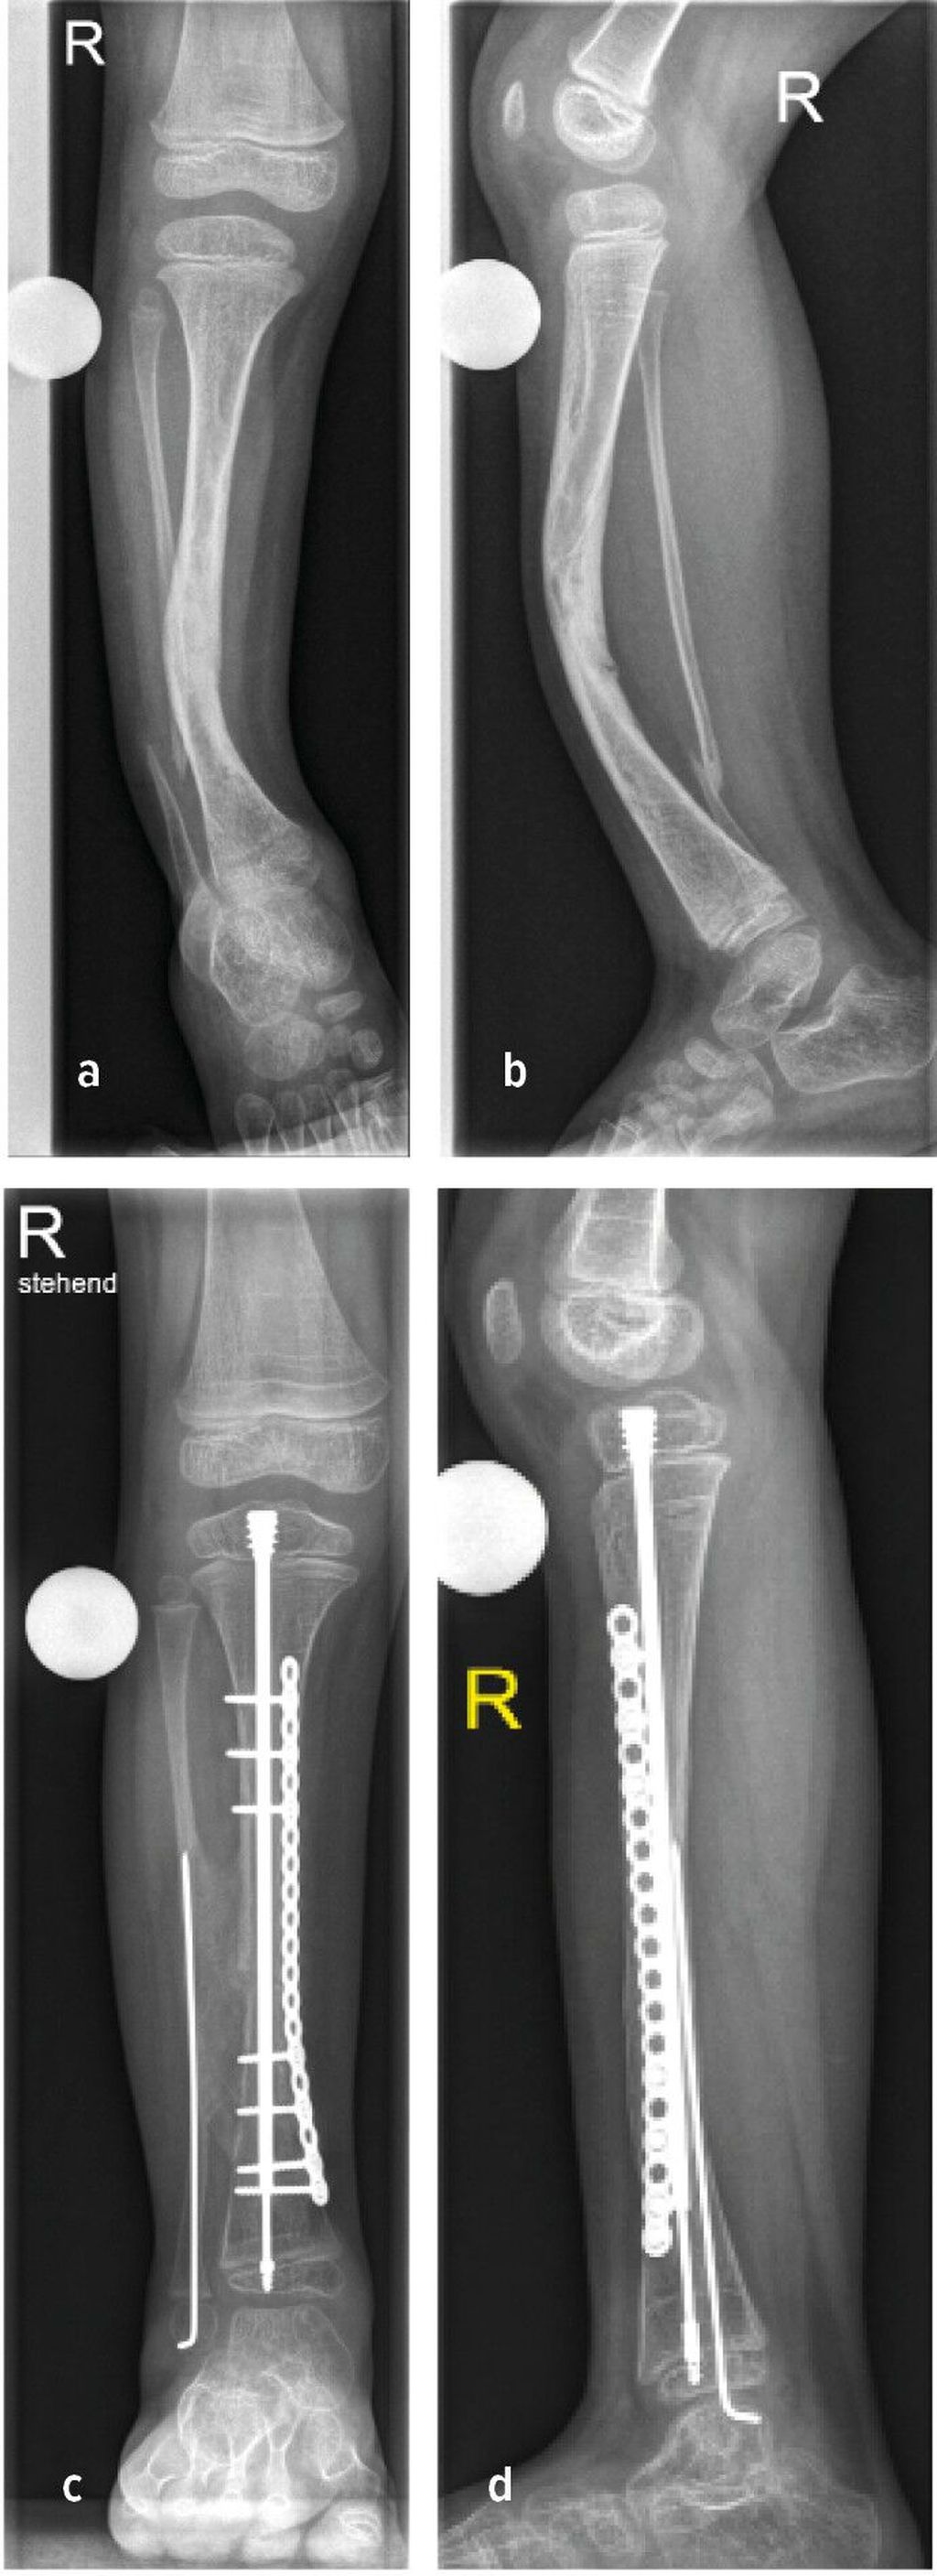

Abb. 1: 6-Jähriger mit unilateraler FH und 4-strahligem Fuß rechts sowie ausgeprägter Beinlängendifferenz vor chirurgischer Rekonstruktion (a–c). Laufende Valguskorrektur und Beinlängenausgleich mittels externen hexapoden Fixateurs mit Fußeinschluss

Die neuere Unterteilung nach Paley bezieht die Sprunggelenkspathologien in die Klassifikation mit ein (vier Typen mit Untergruppen) und gibt auch hier Empfehlung zu operativen Verfahren ab.1 Ziele der chirurgischen Rekonstruktion umfassen die Fußkorrektur mit plantigrader Position, den Ausgleich der Beinlängendifferenz bei Wachstumsabschluss sowie eine neutrale Beinachse. Neben konservativen Maßnahmen wie Schuhzurichtungen und Orthosenversorgung, erfolgt die Korrektur schließlich über chirurgische Verfahren wie Stabilisierungstechniken des Knie- und Sprunggelenkes, Wachstumslenkung sowie beinverlängernde Maßnahmen. Im Fall des 6-jährigen Patienten erfolgten eine Valguskorrektur und ein Beinlängenausgleich mittels externen hexapoden Fixateurs und Fußeinschluss (Abb.1d,e).6 In besonders schweren Fällen mit ausgeprägter Fehlbildung und Hypoplasie des Fußes kann eine Amputation mit anschließender Orthoprothesenversorgung in Betracht gezogen werden.7

Abb. 2: Präoperative (a+b) sowie postoperative Bildgebung (c+d) eines 5-jährigen Patienten mit CPT

Rezente Klassifikation berücksichtigt die Integrität der Tibia und Fibula, die Stellung der distalen Fibula in der Gelenksgabel sowie das Vorhandensein knöcherner Defekte.11 Sowohl konservative Therapie zur Frakturvermeidung als auch operative Verfahren zur Korrektur der Fehlstellung stehen zur Verfügung: Orthesen, Anlage eines externen Fixateurs, intramedulläre Marknagelung, Transfer einer vaskularisierten Fibula oder Durchführung einer sogenannten Cross-Union (X-Union). Abbildung 2b zeigt hierzu den Fall einer Cross-Union-Operation mit Resektion der Pseudoarthrose, guter Knochenbrücke zwischen Tibia und Fibula (Cross-Union), Stabilisierung der Tibia mit intramedullärem Teleskopnagel und Platte, Stabilisierung der Fibula mit Bohrdraht (Abb.2c,d).11,12